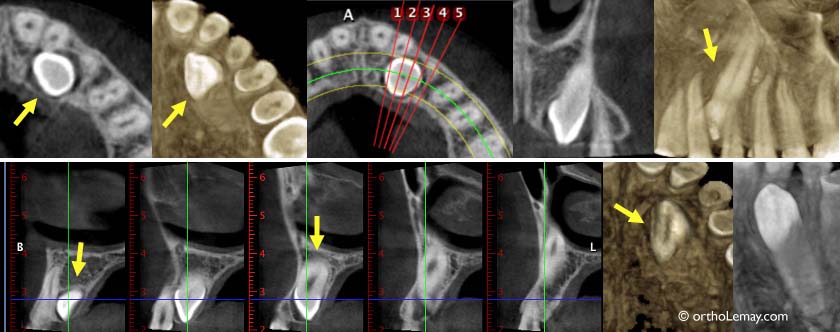

Localisation des dents incluses

Exemple de clichés obtenus à l’aide d’une tomodensitométrie volumique tri-dimensionnelle pour localiser une canine incluse palatine (indiquée par les flèches). Ceci permet de s’assurer que la racine de la latérale n’est pas affectée par la dent incluse.